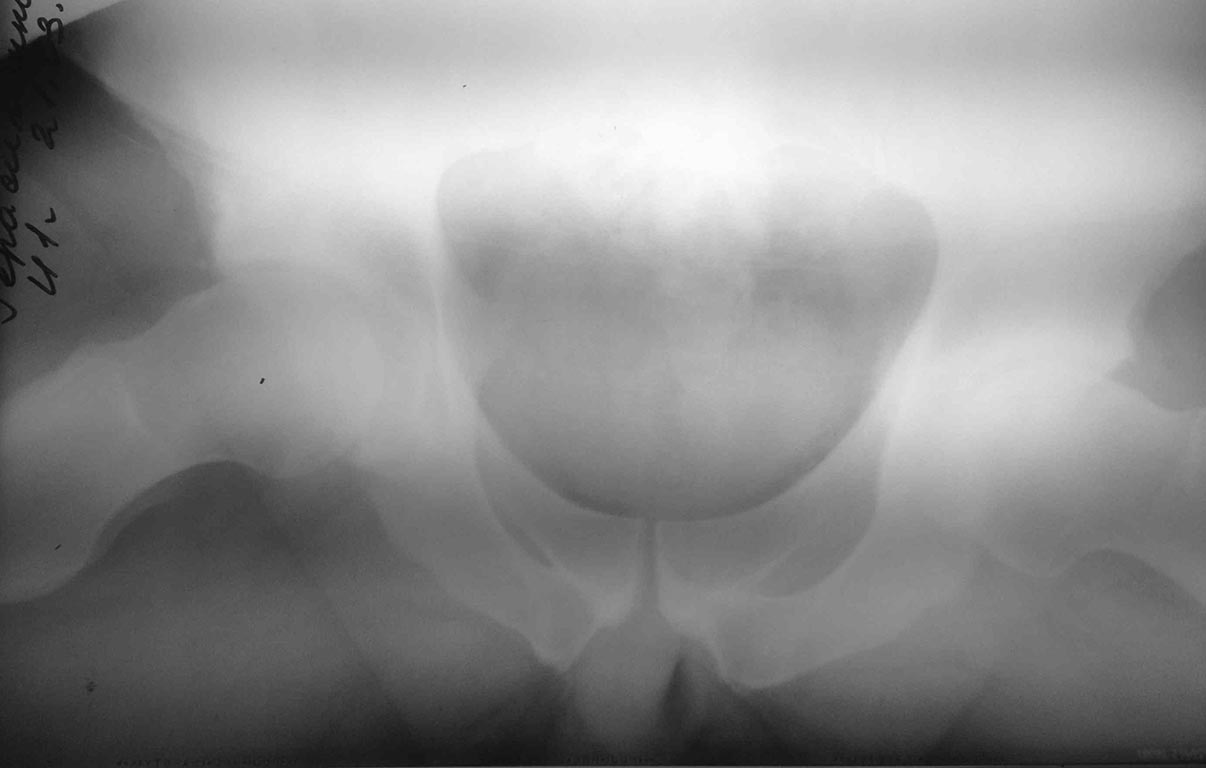

[Ortho] FAI

заранее извиняюсь за качество, в ближайшее время переделаю.